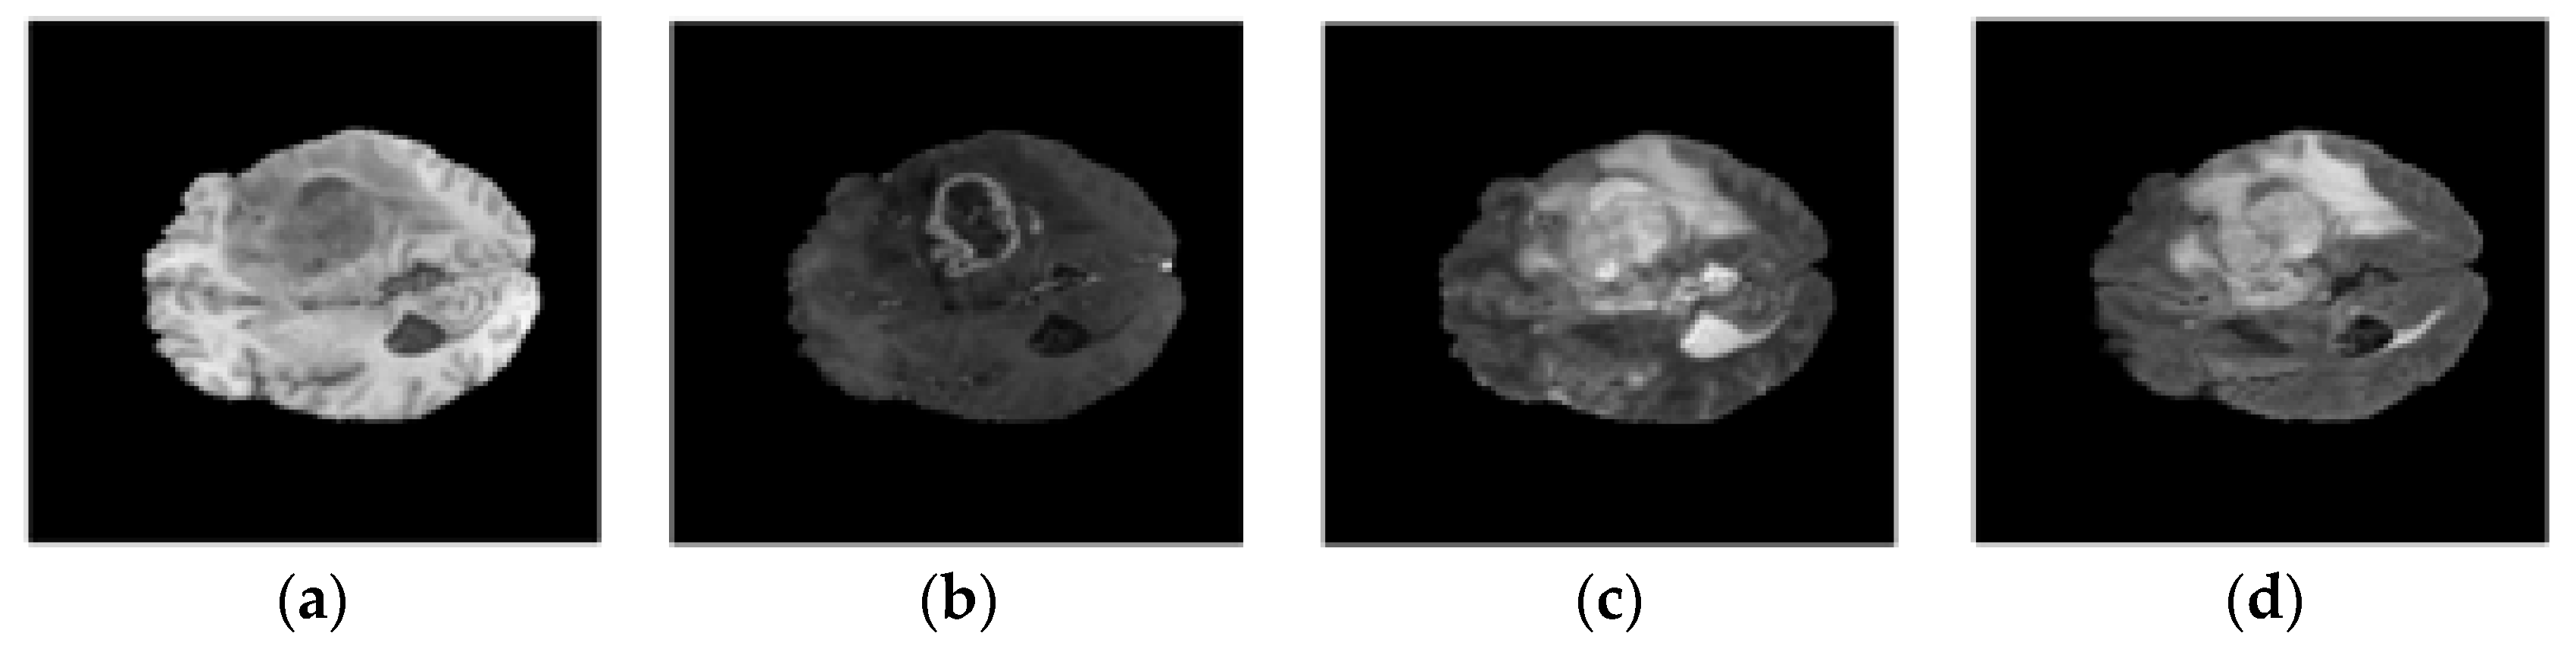

4.2. Dataset Description

4.3. Data Preparation